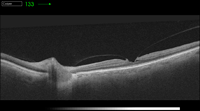

Figura 1. Adhesión vitreomacular.

Figura 2. Tracción vitreomacular.

Figura 3. Tracción vitreofoveolar.

Figura 4. Tracción vitreofoveolar "en meseta".